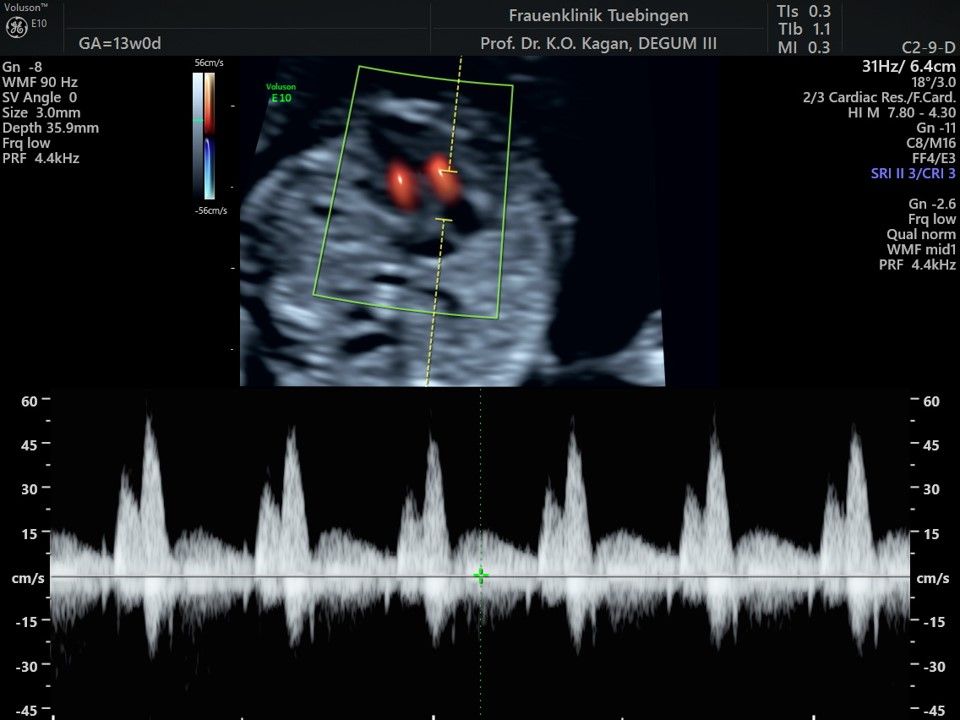

Das Ergebnis der Ultraschalluntersuchung ist wegweisend. Dabei wird der Fet vermessen, die Organe werden untersucht und die sonographischen Marker zur Risikoberechnung für Chromosomenstörungen werden beurteilt. Das sind: die Nackentransparenzdicke, Nasenbein sowie der Blutfluss in der rechten Herzhälfte und im Ductus venosus, einem Gefäß in der Leber des Feten.

Herz